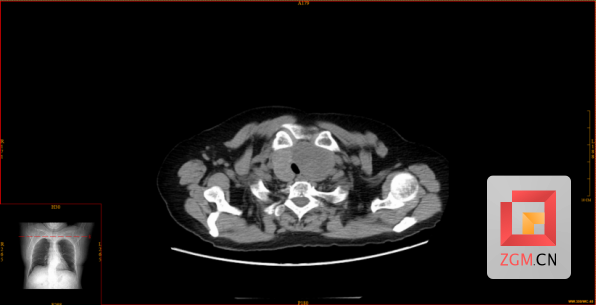

今年71岁的刘阿姨,因“摔伤致踝关节疼痛”被送到市四医院骨科中心救治。住院期间,患者突发气道梗阻,随即出现呼吸、心跳骤停。经过多学科团队的紧急抢救,患者的生命体征和意识已经恢复。随后进行的影像学检查揭示病因:甲状腺左叶存在一巨大肿物,大小约6.4×5.56×4.13cm,气管受压变窄,最窄处仅约0.588cm,已处于窒息高危状态。